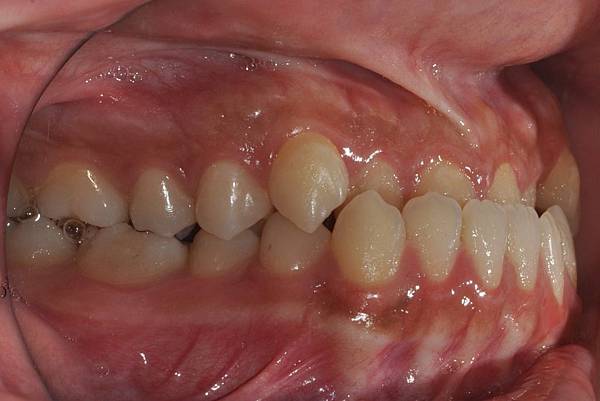

戽斗下唇突出改善案例

本案例因為考量到患者下唇突出

便建議拔除上下四顆小臼齒將

下唇內收

也改善了

前牙錯咬

的問題~

治療前/治療後

-以上案例由林昇進醫師提供